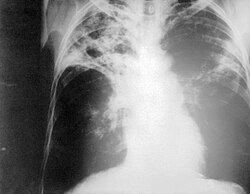

- atlikus krūtinės ląstos rentgenogramą ir joje matant aiškius plaučių audinio pažeidimus;